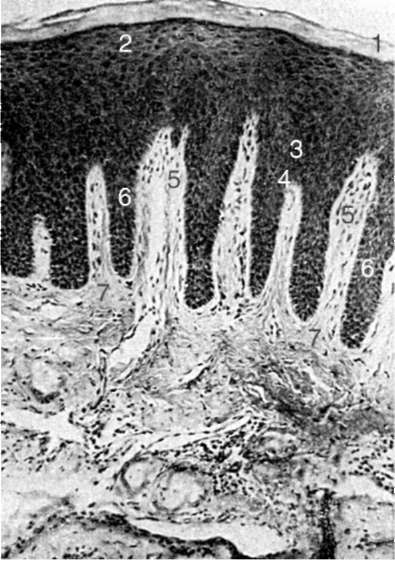

Рис. 4-1. Строение десны человека (Гемонов В.В.): 1 - роговой слой эпителия; 2 - зернистый слой; 3 - шиповатый слой; 4 - базальный слой; 5 - соединительнотканные сосочки; 6 - эпителиальные сосочки; 7 - собственная пластинка слизистой оболочки